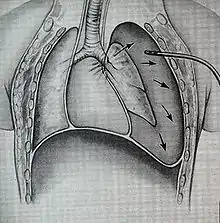

Treatment of TBI varies based on the location and severity of injury and whether the patient is stable or having trouble breathing,[2] but ensuring that the airway is patent so that the patient can breathe is always of paramount importance.[10] Ensuring an open airway and adequate ventilation may be difficult in people with TBI.[3] Intubation, one method to secure the airway, may be used to bypass a disruption in the airway in order to send air to the lungs.[3] If necessary, a tube can be placed into the uninjured bronchus, and a single lung can be ventilated.[3] If there is a penetrating injury to the neck through which air is escaping, the trachea may be intubated through the wound.[10] Multiple unsuccessful attempts at conventional (direct) laryngoscopy may threaten the airway, so alternative techniques to visualize the airway, such as fiberoptic or video laryngoscopy, may be employed to facilitate tracheal intubation.[10] If the upper trachea is injured, an incision can be made in the trachea (tracheotomy) or the cricothyroid membrane (cricothyrotomy, or cricothyroidotomy) in order to ensure an open airway.[6] However, cricothyrotomy may not be useful if the trachea is lacerated below the site of the artificial airway.[10] Tracheotomy is used sparingly because it can cause complications such as infections and narrowing of the trachea and larynx.[26] When it is impossible to establish a sufficient airway, or when complicated surgery must be performed, cardiopulmonary bypass may be used—blood is pumped out of the body, oxygenated by a machine, and pumped back in.[26] If a pneumothorax occurs, a chest tube may be inserted into the pleural cavity to remove the air.[12]